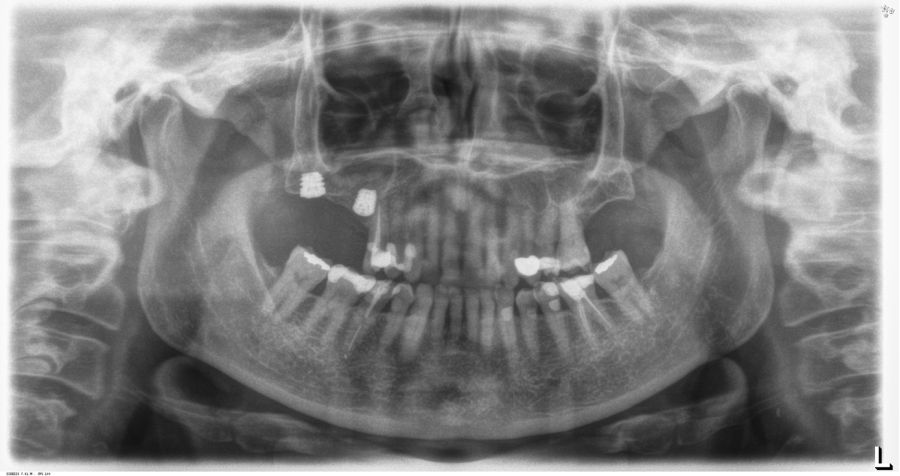

La inserción de los implantes fue realizada por un mismo cirujano, mediante la técnica de fresado biológico, a bajas revoluciones, sin irrigación. Con esta técnica todo el hueso recolectado es embebido en PRGF-Endoret durante la cirugía para posteriormente ser utilizado como injerto óseo particulado17-19. El fresado final de la cortical sinusal se realizó con la fresa de corte frontal (ideada para esta técnica) que permite la retirada del suelo del seno maxilar sin dañar la membrana de Schneider6-7. Una vez la membrana es accesible mediante la perforación crestal, se despega, se inserta el implante con el motor quirúrgico fijado a 25 Ncm y 25 rpm finalizando la inserción del implante con la llave dinamométrica (Figura 1). El implante eleva lentamente la membrana a la vez que es insertado en el neo-alveolo.

Una vez finalizada la cirugía se realiza una radiografía periapical con paralelizador, que se utilizó como punto de partida. Los pacientes acudieron posteriormente para la realización nuevas radiografías de control, tomadas con la misma técnica y sobre las que se realizaron las mediciones necesarias para comprobar la estabilidad y pérdida ósea crestal de los implantes. La medición de la pérdida ósea marginal se realizó en la última radiografía periapical realizada con posicionador de seguimiento. Una vez obtenida la radiografía en formato digital es calibrada mediante un software específico (ImageJ software- Rasband, W.S., ImageJ, U. S. National Institutes of Health, Bethesda, Maryland, USA, https://imagej.net/ij/, 1997-2018) a través de una longitud conocida en la radiografía como es el implante dental. Una vez se introdujo la medida de calibración, el programa informático realiza un cálculo basado en esta medida para eliminar la magnificación, pudiendo realizar mediciones lineales exentas de este error (Figura 2). La pérdida ósea de los implantes fue medida en dos puntos: mesial y distal en cada uno de los casos (Figura 3).

Para la estimación de la ganancia en altura sobre el ápice se realizó un CBCT previo a la carga del implante y al año de carga. Posteriormente, el volumen ganado se monitorizó en las radiografías periapicales al igual que la pérdida ósea crestal.

Fueron reclutados 13 pacientes que cumplieron los criterios de inclusión en los que se insertaron 30 implantes. La edad media fue de 70 +/- 1 años en el momento de la cirugía y 10 de los pacientes fueron hombres. El tiempo medio de seguimiento desde la carga fue de 126 meses (+/- 1,79; Rango 120- 150 meses). Los diámetros, longitudes y posiciones de los implantes se muestran en la Figura 4. La altura media de la cresta residual fue de 4,86 mm (+/-0,97; rango 1,95-5,88 mm). El torque de inserción medio de los implantes fue de 26,45 Ncm (+/- 1,89). Una vez insertados y cargados los implantes, la altura media final fue de 9,68 mm (+/- 2,66; rango 6,74-13,11 mm), lo que supone una ganancia promedio de 5 mm. A los 10 años, se observa una disminución media de la altura ósea ganada en los implantes en conjunto de 0, 29 mm (+/- 0,77).

En las Figuras 5-16 se muestra uno de los casos incluidos en el estudio.